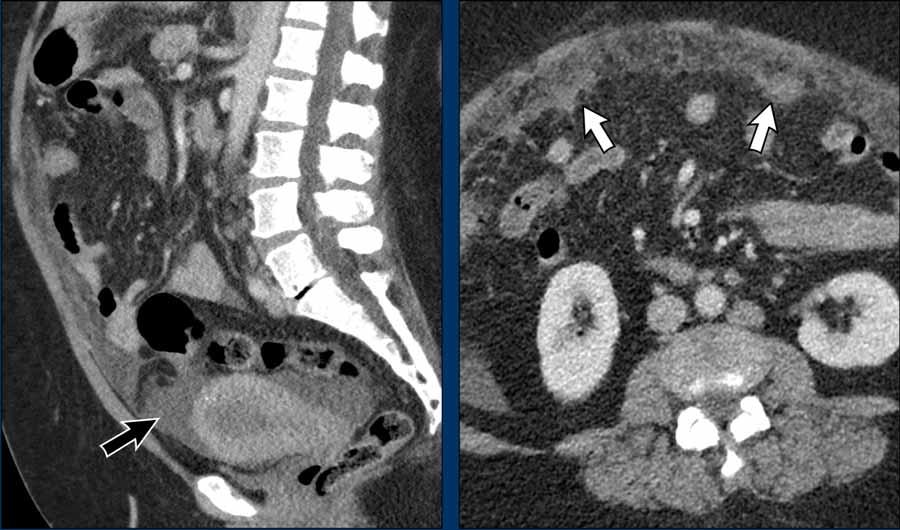

Di căn theo đường máu

Ung thư nội mạc tử cung thường di căn nhất đến phúc mạc hoặc phổi. Không hiếm gặp trường hợp tổn thương tại chỗ còn tương đối khu trú nhưng đã có sự lan rộng khối u theo đường máu.

Hình ảnh

Mặc dù khối u nội mạc tử cung khó nhận diện trên CT (cần nhớ rằng để phân giai đoạn tại chỗ cần dùng MRI), khối u có vẻ còn khu trú trong tử cung mà không có dấu hiệu khối lan ra ngoài tử cung.

Tuy nhiên, có các dấu hiệu rõ ràng của di căn phúc mạc với cổ trướng lan tỏa (mũi tên đen) và hình ảnh bánh mạc nối (omental cake) rõ ràng (mũi tên trắng).